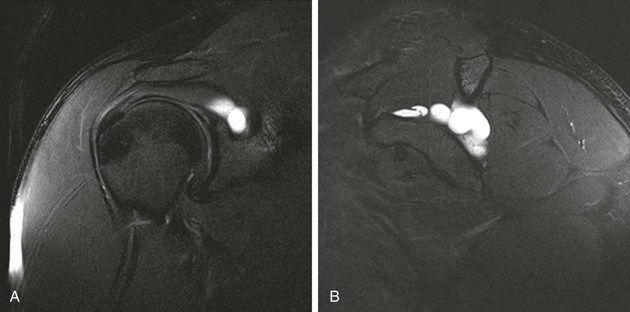

An intramuscular cyst within the rotator cuff (Fig. 44-27, A and B) has been described as a finding associated with small full-thickness tears or partial-thickness articular-sided tears of the rotator cuff.114 Intramuscular cysts are similar to paralabral cysts of the shoulder or meniscal cysts of the knee. Fluid leaks through a defect in the cuff and tracks in a delaminating fashion along the fibers of the tendon, resulting in a fluid collection contained within either the muscle or fascia of the rotator cuff. These cysts have been reported in the supraspinatus, infraspinatus, and subscapularis muscles and appear as oval lobulated collections of low signal intensity on T1-weighted images and high signal intensity on T2-weighted images. Identification of an intramuscular cyst of the rotator cuff should prompt a thorough search for a small associated cuff tear.